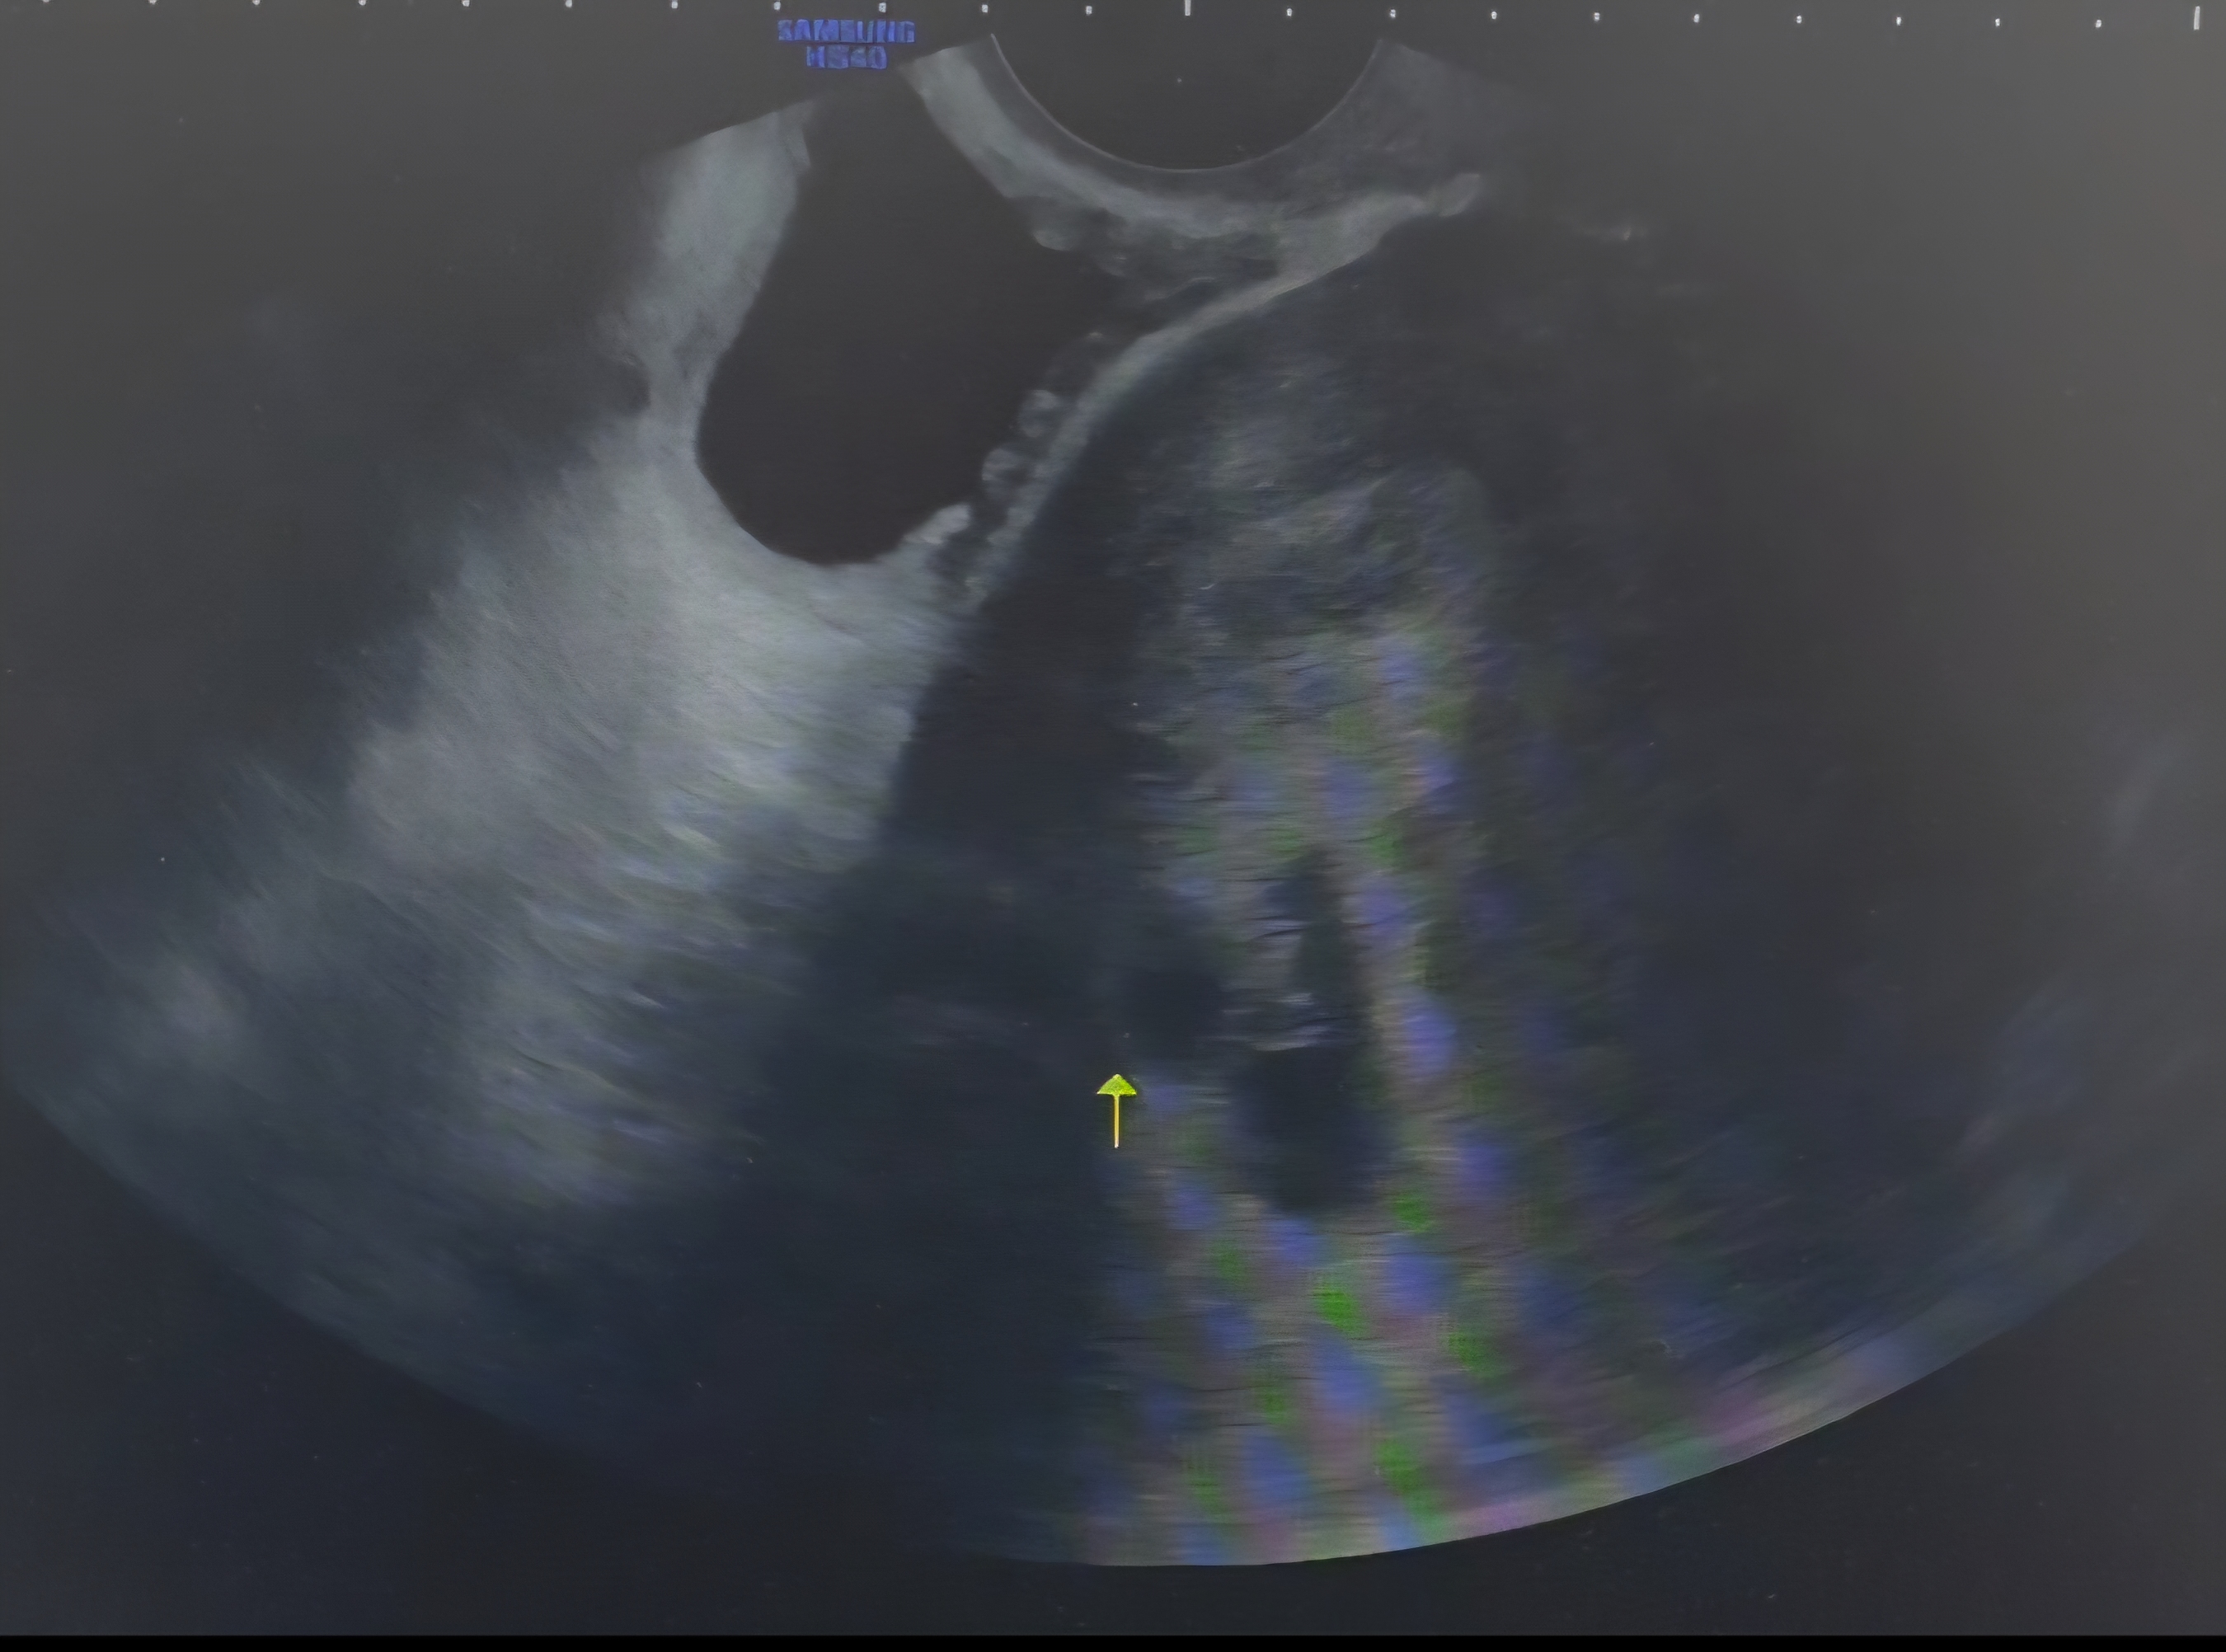

6주차1일 초음파 아기집 2개? 1개?

6주차1일 첫초음파 보고 왔어요^^ 아기집 큰거에는 아기, 난황 보이고 심장소리까지 다들었는데 하나가 더 보이는것 같기도 하고 아닌것같다고 하시면서 의사선생님도 긴가민가 하시더랑구요ㅠㅠ 일단 2주후에 다시 내원하기로 했습니다😭어떻게 보이세요??